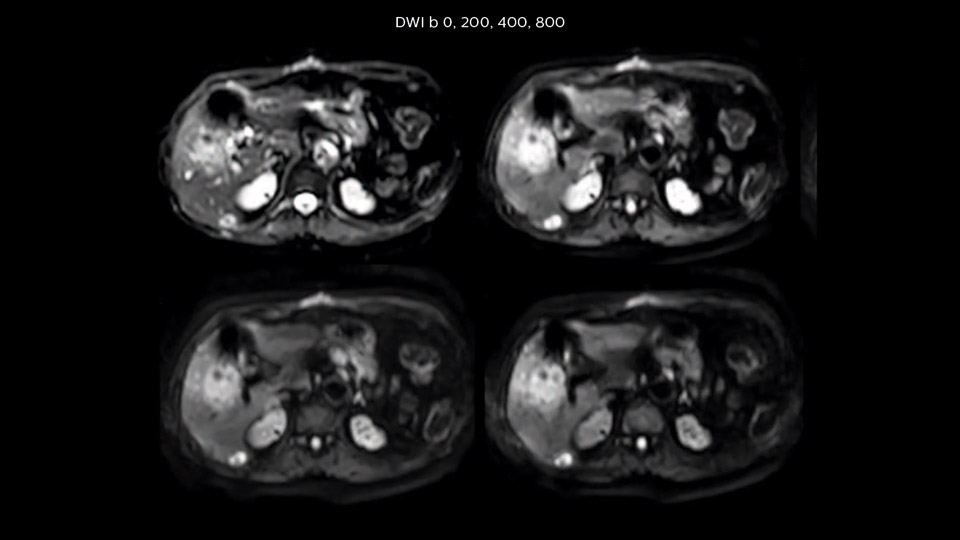

In this example the image quality of the MultiVane XD images is evidently better than in the images without MultiVane XD. Ingenia 1.5T with dS Torso coil solution.